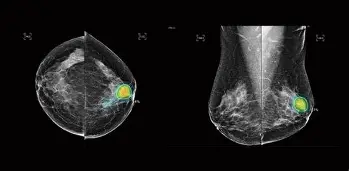

Chụp X-quang vú (Mammography) là phương pháp sử dụng tia X liều thấp để tạo ra hình ảnh chi tiết của mô tuyến vú. Đây là kỹ thuật được coi là “tiêu chuẩn vàng” trong tầm soát ung thư vú, đặc biệt đối với phụ nữ từ 40 tuổi trở lên.

Trong khi siêu âm vú thường phù hợp với phụ nữ trẻ có mô vú dày, thì chụp X-quang vú lại có ưu thế trong việc phát hiện vi vôi hóa – dấu hiệu sớm của ung thư vú mà siêu âm khó nhận diện.

Hình ảnh từ chụp X-quang vú giúp bác sĩ phát hiện:

Vi vôi hóa: Dấu hiệu sớm nhất của ung thư vú.

Khối u: Vị trí, kích thước, bờ viền.

Tổn thương lành tính: Nang, u xơ, thay đổi mô mỡ.

Dấu hiệu bất thường khác: Thay đổi cấu trúc mô vú, hạch vùng nách.

Kết quả thường được phân loại theo hệ thống BI-RADS, từ đó bác sĩ sẽ đưa ra hướng xử trí tiếp theo: theo dõi, làm thêm siêu âm vú, sinh thiết hoặc đưa vào chương trình tầm soát ung thư vú.